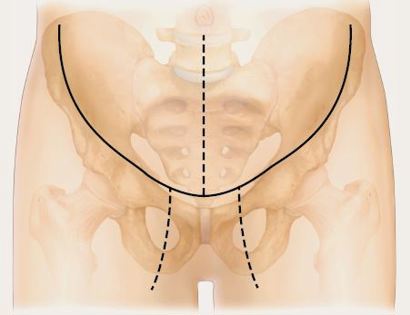

Incision

An incision is made that curves across the top of the femur bone.